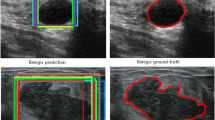

Automated detection of Gallbladder Cancer (GBC) from Ultrasound (US) images is an important problem, which has drawn increased interest from researchers. However, most of these works use difficult-to-acquire information such as bounding box annotations or additional US videos. In this paper, we focus on GBC detection using only image-level labels. Such annotation is usually available based on the diagnostic report of a patient, and do not require additional annotation effort from the physicians. However, our analysis reveals that it is difficult to train a standard image classification model for GBC detection. This is due to the low inter-class variance (a malignant region usually occupies only a small portion of a US image), high intra-class variance (due to the US sensor capturing a 2D slice of a 3D object leading to large viewpoint variations), and low training data availability. We posit that even when we have only the image level label, still formulating the problem as object detection (with bounding box output) helps a deep neural network (DNN) model focus on the relevant region of interest. Since no bounding box annotations is available for training, we pose the problem as weakly supervised object detection (WSOD). Motivated by the recent success of transformer models in object detection, we train one such model, DETR, using multi-instance-learning (MIL) with self-supervised instance selection to suit the WSOD task. Our proposed method demonstrates an improvement of AP and detection sensitivity over the SOTA transformer-based and CNN-based WSOD methods. Project page is at https://gbc-iitd.github.io/wsod-gbc.